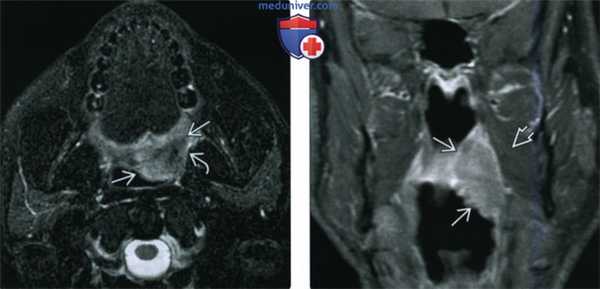

(Слева) При МРТ Т2ВИ в аксиальной проекции визуализируется патологически измененный солидный лимфоузел уровня IIА. Определяется также неявное асимметричное утолщение миндалины, которое, хотя и может быть вариантом нормы, но при отсутствии других изменений, которые могли бы объяснить лимфаденопатию, позволяет порекомендовать биопсию.

(Справа) При МРТ Т2ВИ FS в корональной проекции у этого же пациента определяется гиперинтенсивный сигнал в язычной миндалине справа. Несмотря на то, что асимметрия укладывается в границы нормы, злокачественная лимфаденопатия делает ее подозрительной находкой. В итоге подтвердился ВПЧ(+) ПКР язычной миндалины.